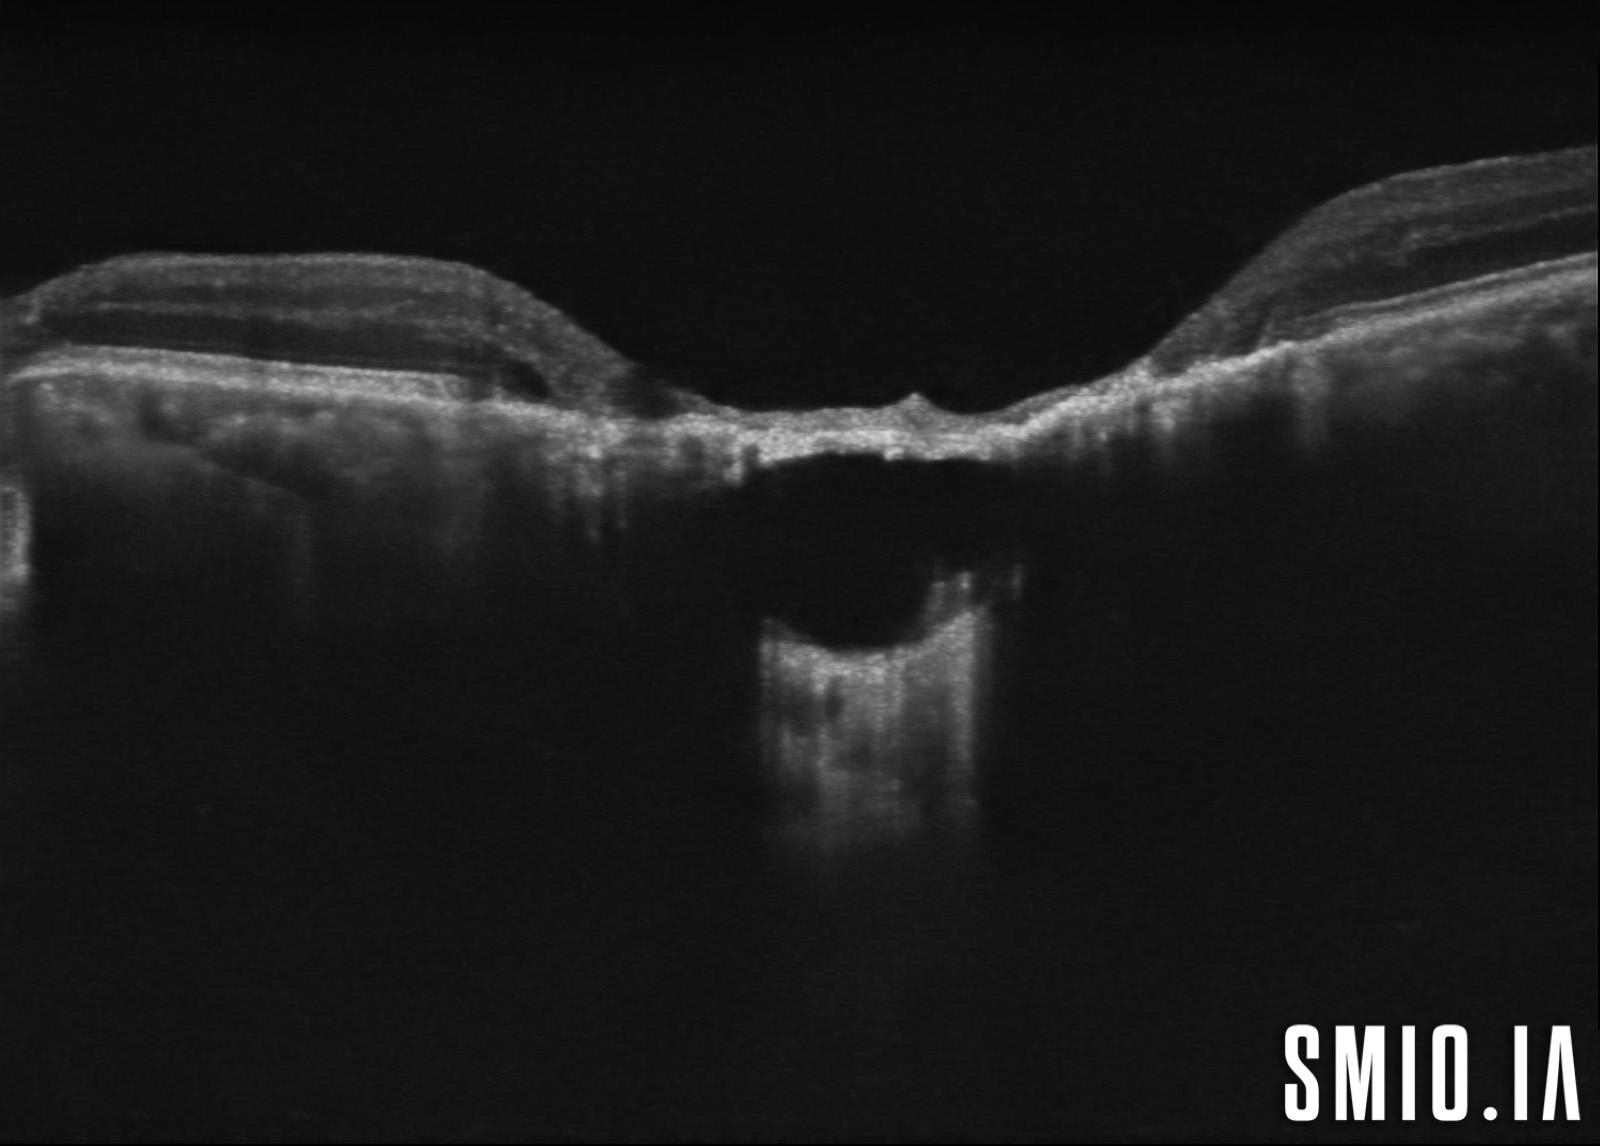

Description: L'image stéréo d'une cicatrice choriorétinienne de toxoplasmose oculaire congénitale avec l'OCT à travers la lésion a démontré une grande lésion choriorétinienne excavée de colobome avec une cavitation intrachoroïdienne